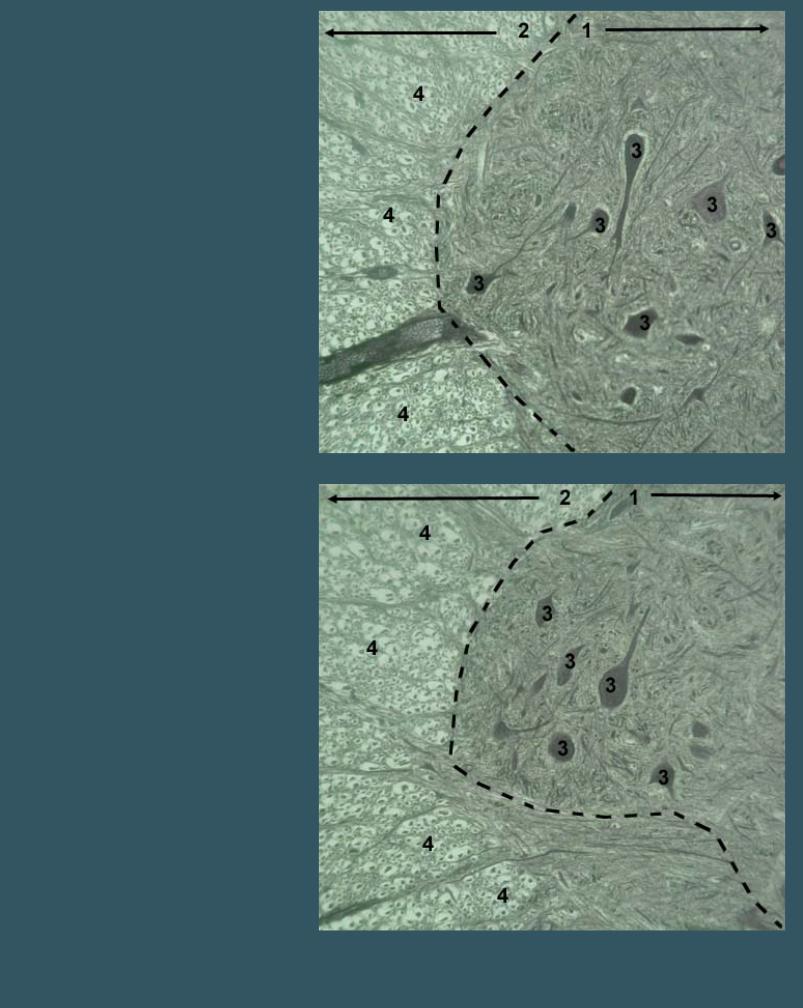

СПИННОЙ МОЗГ

Импрегнация нитратом серебра

1 - серое вещество (передние рога)

2 - белое вещество

3 - тела нейронов

4 - нервные волокна в поперечном срезе

(проводящие пути)

МИКРОСКОПИЧЕСКИЕ ФОТОГРАФИИ - НЕРВНАЯ СИСТЕМА

СПИННОЙ МОЗГ

Импрегнация нитратом серебра

1 - серое вещество (передние рога)

2 - белое вещество

3 - тела нейронов

4 - нервные волокна в поперечном срезе

(проводящие пути)